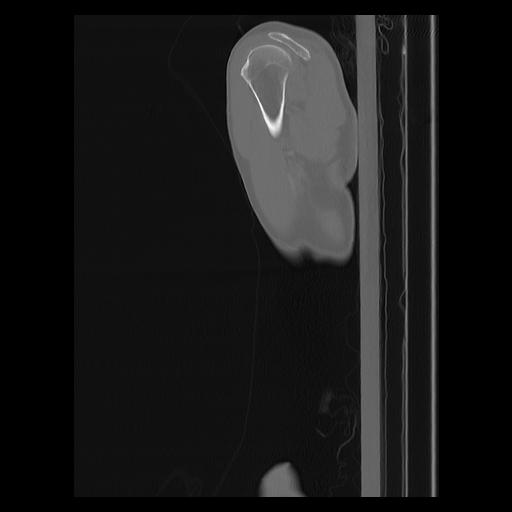

33 PULMON,CE,Sagittal,3.000,PULMON,Sagittal,